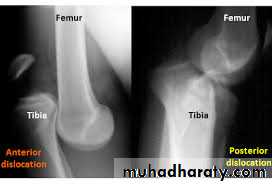

Knee dislocation

The knee can be dislocated only by considerable violence, as in a road accident.The cruciate ligaments

and one or both lateral ligaments are torn.There is sever swelling ,

bruisesand knee deformity.

The circulation and sensation in foot must be examined

to exclude popliteal vessels and nerve injuriesTreatment :

URGENT reduction by closed or open reduction

followed bysplinting the knee in 15 degrees flexion for 12 weeks and

physiotherapy.Repeated check of circulation is essential,

If the joint is unstable anterior external fixator applied.If there is open wound or vascular injury the opportunity is taken to repair the ligaments and capsule.

When swelling subsides, a cast is applied for 12 weeks.

Quadriceps exercises encouraged from the start, and knee range of motion exercises after plaster removal.

Complications:

Early complications arearterial injures and nerve injuries.

Late complicationare chronic instability.